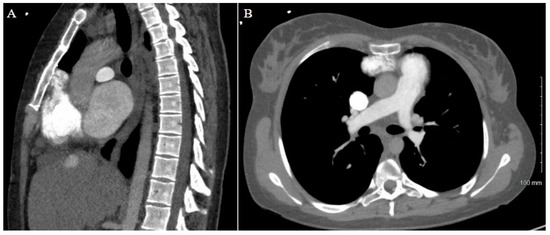

Figure 1. Patient 1 CT chest. (A) Sagittal view and (B) axial view reveal extensive adhesions between LVAD outflow graft and superior retrosternum. (C) 3D reconstruction with labeled structures LVAD outflow graft (a), sternum (b), ascending aorta (c), aortic arch (d), and descending aorta (e) highlighting the point of maximal LVAD graft–sternal contact (white arrow).

As expected, the patient’s extensive history of cardiac surgery with three prior sternotomies made for a complicated reentry to the thorax. A review of the preoperative chest CT demonstrated tight adhesions between the LVAD outflow graft and the superior retrosternal surface (Figure 1). The precise anatomic level of these adhesions and the safe portion of the sternum without adhesions was localized by leveraging the sternotomy wires as landmarks. Intraoperatively, a partial sternotomy was made from the xiphoid process, inferiorly, until the third intercostal space (Figure 2A). At this point, the outflow graft was mobilized, and aortic cannulation was established via the LVAD outflow graft, and IVC drainage was established via percutaneous peripheral femoral vein access. The inferior portion of the sternum was then carefully dissected away from the heart, mediastinum, and LVAD outflow graft. Due to dense adhesions between the LVAD outflow graft and the sternum, a section of periosteum was left attached to the graft.

A careful review of the CT imaging was crucial to the preoperative planning of both cases of stepwise sternotomy. The preoperative imaging identified not only structures at risk of reentry injury but also the specific site at which this risk was present. By utilizing landmarks identified in the imaging, we were able to formulate an individualized two-stage approach to reentry that was safe for each patient. With one patient demonstrating inferior retrosternal adhesions and one demonstrating superior retrosternal adhesions, understanding this patient-specific anatomy was necessary to strategize a safe approach to stepwise sternotomy.